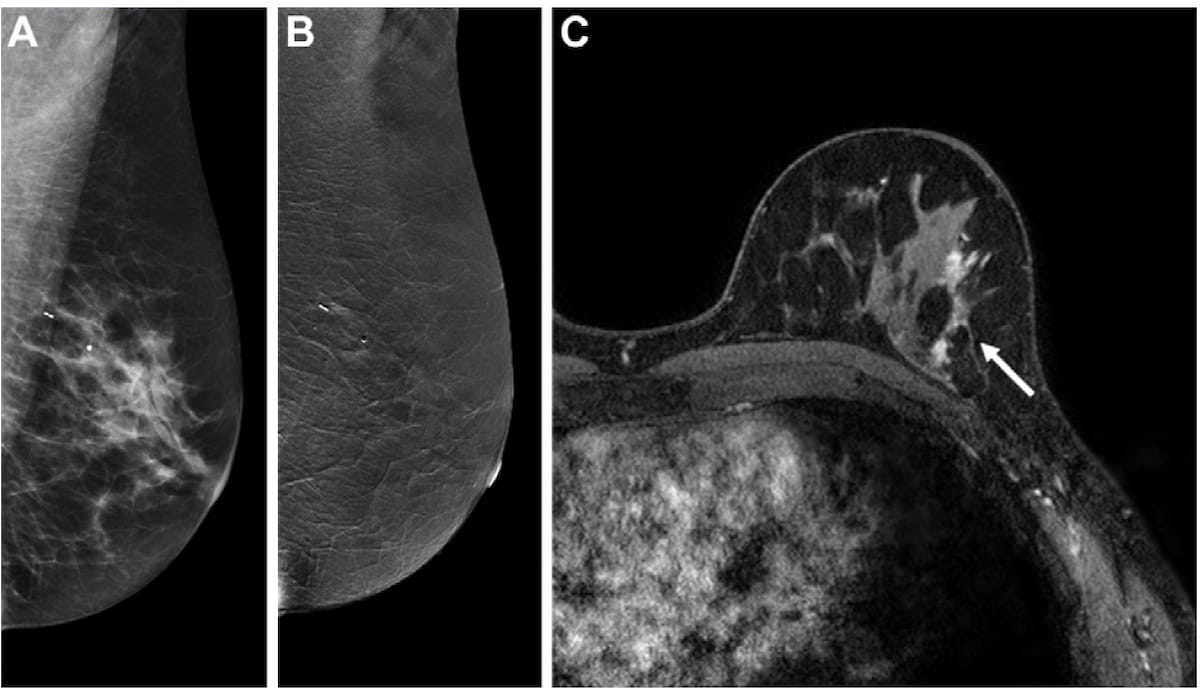

Las imágenes de arriba de una participante del estudio de 61 años con una pareja y el locus del gen 2 del cáncer de mama (PALB-2) revelan resultados CEM falsos negativos (A y B) y resultados positivos verdaderos usando MRI/mama abreviada. RM (C). (Imágenes cortesía de rayos.)

La resonancia magnética estándar y ABMRI tuvieron tasas de sensibilidad significativamente más altas (88,9 por ciento y 100 por ciento, respectivamente) que CEM (61,1 por ciento). Los investigadores también esperaban una mayor detección de cáncer por cada 1000 exploraciones con MRI estándar (36,6) y ABMRI (32,5) en contraste con CEM (22,4).

Sin embargo, la tasa de especificidad para CEM fue más alta (87,8 % en comparación con 75,7 % para ABMRI y 80,2 % para MRI estándar, según los autores del estudio. Los investigadores notaron que la tasa de recuperación para CEM fue más baja (14 %) que para MRI estándar (22,8 por ciento) y ABMRI (26,6 por ciento) Los autores del estudio también predijeron una disminución significativa en el número de recomendaciones de biopsia falsamente positivas por cada 1000 exámenes para CEM (65) en comparación con la resonancia magnética estándar (162,6) y ABMRI (180,9).